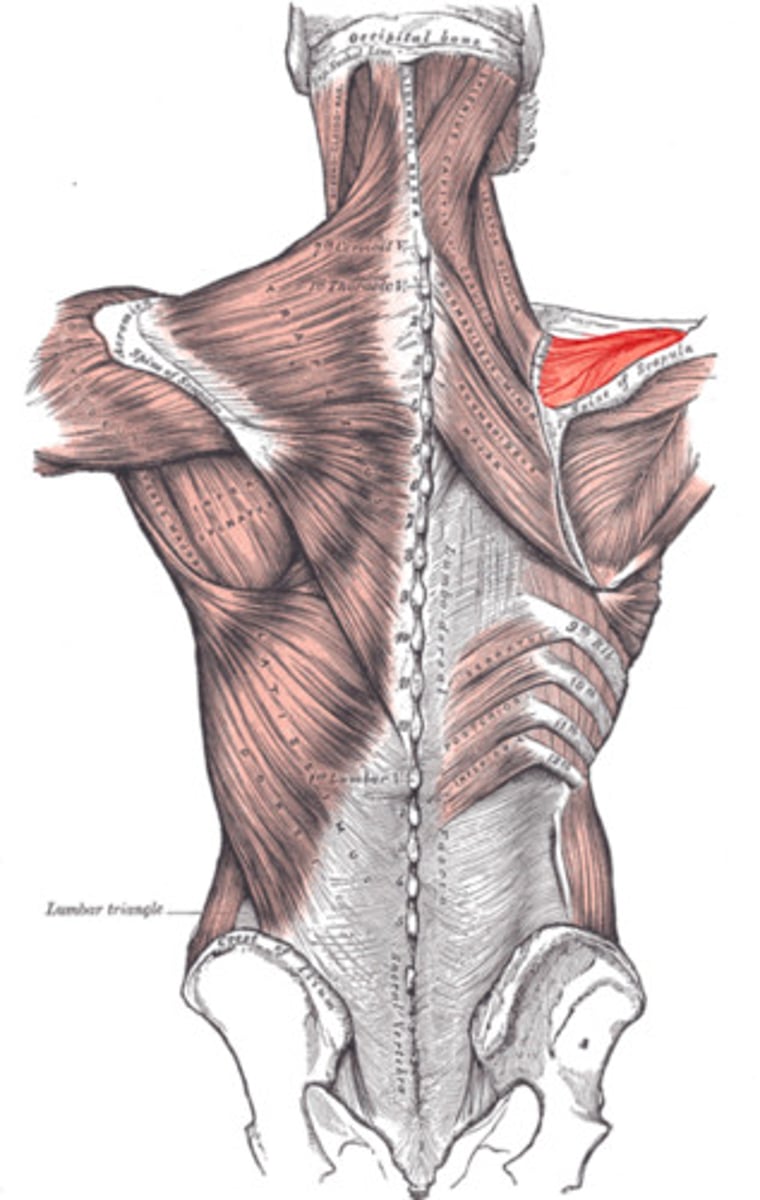

(Posterior axioappendicular and scapulohumeral muscles:) Superficial posterior axioappendicular muscles (extrinsic shoulder)

Trapezius and Latissimus dorsi

(Superficial posterior axioappendicular muscles (extrinsic shoulder):) Trapezius

-Elevates, depresses, and retracts scapula

-Accessory nerve (CN XI)

(Superficial posterior axioappendicular muscles (extrinsic shoulder):) Latissimus dorsi

-Extends, adducts, and medially rotates humerus

-Thoracodorsal n. (C6 - C8)

(Posterior axioappendicular and scapulohumeral muscles:) Deep posterior axioappendicular muscles (extrinsic shoulder)

Levator Scapulae and Rhomboid minor and major

(Deep posterior axioappendicular muscles (extrinsic shoulder):) Levator Scapulae

-Elevates and rotates scapula

-Dorsal scapular n. (C5)

(Deep posterior axioappendicular muscles (extrinsic shoulder):) Rhomboid Minor and Major

-Retract and rotates scapula

-Dorsal scapular n. (C5)